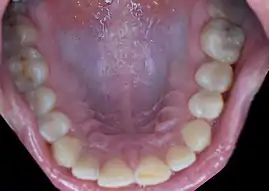

Rugae can appear in the following locations in humans:

- Hard palate immediately behind the upper anterior teeth